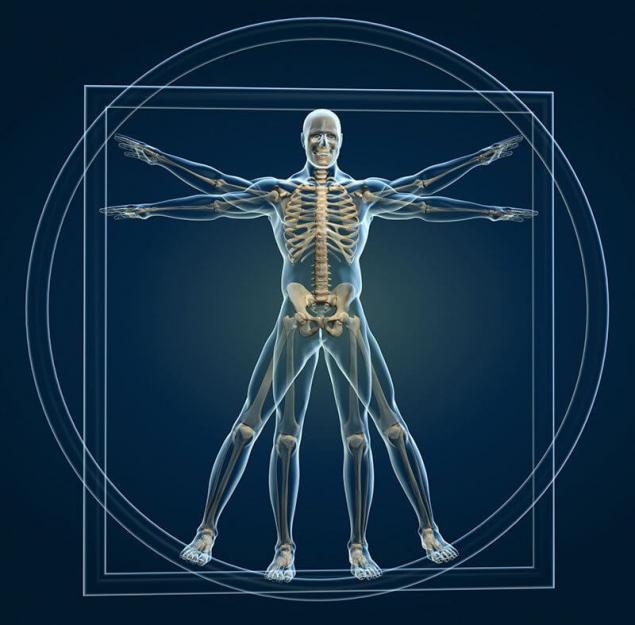

核磁共振

核磁共振扫描,人体脊椎

可以帮助我们清楚的看到人体中的异常,核磁共振的基本原理就是人体